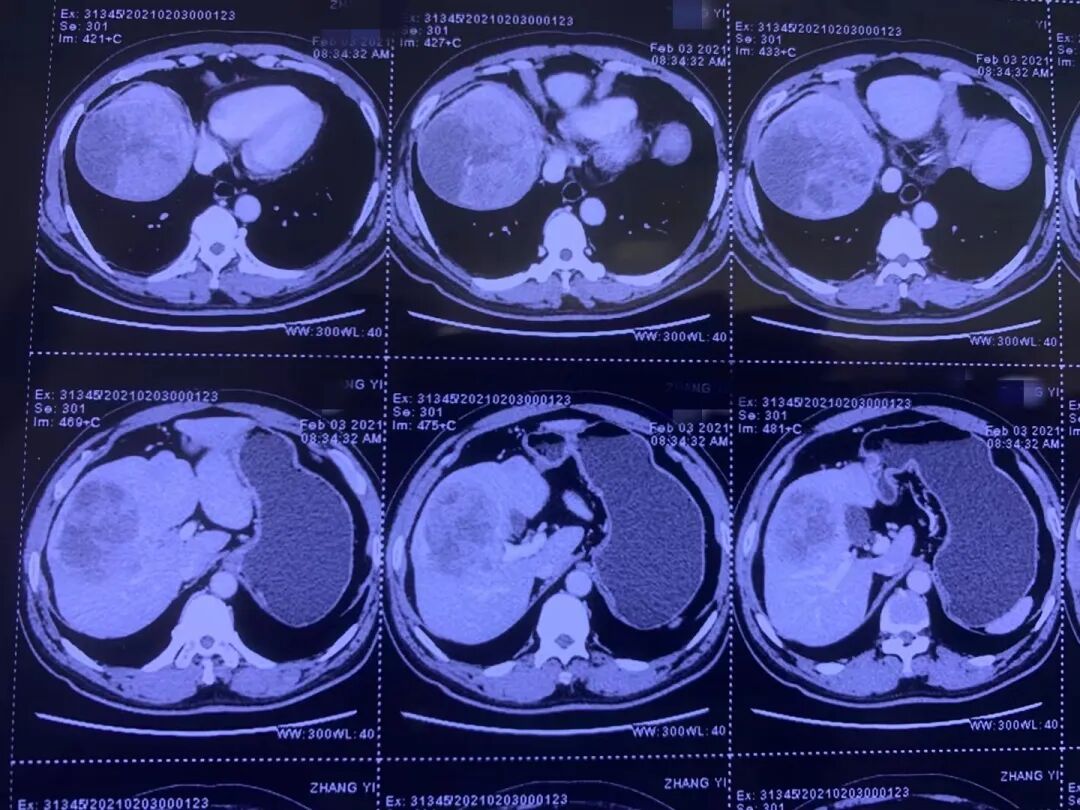

今天是第21个“全国爱肝日”,主题为“爱肝护肝、防治结合、遏制肝炎”。肝癌是我国致死率极高的癌症之一,发病率第四位、死亡率第二位,由于肝癌早期无症状,患者感受不到疼痛,等有症状前来医院就诊时,约70%的患者已经处于中晚期,失去了根治手术机会,被称为“沉默的杀手”,所以人们在日常生活中要充分重视对肝脏的保护。 日前,哈医大二院普外科一病房(胆胰外科)副主任邰升教授团队,为一位本来无法进行手术的肝癌晚期患者,在进行了转化治疗之后,将不可能手术变为了可能,成功根治性切下直径约14厘米的巨大肝肿瘤,延长了患者生命。 邰升教授(右)在进行手术 丙肝病史十余年 身体无明显异常 却被查出巨大肝肿瘤被判“死刑” 今年56岁的刘先生(化姓)有吸毒史和丙肝病史10多年,在成功戒毒后,最近这几年里他闲来无事,就喜欢约上好友们聚会喝酒,平均每天都要喝六瓶啤酒。在三个月前,他突然出现尿频的症状,便在家附近的医院进行了检查,结果让他大吃一惊,因为身体无其他异常,他以为是泌尿系统出了问题,没想到却被医院告知肝上有个大东西,需要到正规的大医院进一步检查。 这让刘先生一下子慌了神,经过多方打听咨询后,他选择来到了哈医大二院胆胰外科。经过全面的检查,确诊刘先生右肝有一个直径约14厘米的肿瘤,肿瘤大到已经侵犯到左肝内叶、门静脉癌栓。 刘先生术前ct片子肿瘤直径达14厘米 胆胰外科副主任邰升教授表示,肿瘤太大,而且肿瘤已经长到门静脉里了,手术切除后剩余的肝脏无法满足人体需求,很大几率会发生肝功能衰竭。同时,因肿瘤体积及活性负荷大,即使剩余肝体积足够承受肝癌切除,术后短期复发率也相当高。刘先生面临的是严重不足的肝体积和极高的肿瘤活性负荷“双重困境”。 手术切除一直是实现肝细胞癌根治和获得长期生存的最重要手段。但是,约70%的肝癌病人在确诊时已属中晚期,失去手术机会。对于中晚期的肝癌,丧失手术机会并不是代表着丧失治疗机会。随着医疗技术的发展,近两年上市的靶向治疗和免疫治疗极大提高了肝癌的治疗效果,通过多学科联合治疗(MDT)能够为众多中晚期肝癌患者制定大幅延长生存期的科学治疗方案。而针对伴有门静脉或肝静脉癌栓等不可切除的中晚期肝癌,目前正在兴起转化治疗。 邰升教授介绍,转化治疗是一种采用多学科诊疗模式(MDT)的治疗方法,通过局部与全身相结合的综合治疗方式设法杀伤或抑制肿瘤,起到缩小肿瘤、降低肿瘤活性和降低肿瘤分期的目的,有望使无法切除的肿瘤转变为可切除肿瘤。 当刘先生了解到转化治疗时,仿佛抓住了救命稻草,愿意放手一搏,积极配合。胆胰外科与化疗科的专家们对此病例进行了集体讨论,通过仔细阅览影像学资料,大家一致认为直接手术无法达到根治可能,可以考虑转化治疗。 化疗科为刘先生制定了免疫治疗和靶向治疗联合的帕博利珠单抗与仑伐替尼的组合(“可乐”组合)。在经过三个周期的转化治疗后,经过CT检查发现,肿瘤缩小3厘米,门静脉癌栓也已经退缩到肝内,根治性切除肿瘤有了希望。 最终,邰升教授带领团队凭着丰富的经验和熟练的操作,将巨大肝肿瘤完整切除。术后刘先生恢复的非常快,病理表示肿瘤细胞病灶大量坏死,癌症组织已经被纤维组织代替。手术切缘也是没有肿瘤细胞残留,在没有接受风险巨大的大量肝切除的情况下,达到了根治性切除的标准。 邰升教授强调,转化治疗的概念一是针对肿瘤太大,但无全身转移的患者,可以在术前进行转化治疗,缩小肿瘤,将不可能手术变为可能;二是对因为乙肝、肝硬化等原因,导致肝功能不好的患者,可以术前进行一些保肝、护肝的治疗;三是由于肿瘤太大,剩余肝体积不够维持正常机体生存需要,因而通过一些方法养大健康肝后再进行手术。 他指出,对于“转化”还可以理解为是外科医生们手术水平的提高,以及对于治疗理念的转化,从"应切尽切"转变为“该出手时才出手”。近二十年来,肝癌防治在理念上有了很大的提升,尤其是中晚期肝癌的治疗理念,临床提出了转化治疗、新辅助治疗及全程管理等理念。而最大的理念改变是,我们慢慢认识到肝癌是一个以局部表现为主的全身性疾病,既然是全身性疾病,局部联合系统治疗就成为了我们治疗的主流模式。这种主流模式贯穿于手术前和手术切除后的全程管理;此外,另外一个较大的理念改变是高度统一的多学科团队,肝胆胰外科、介入科、影像科、化疗科等多学科联合,要以患者的生存获益为原则进行最佳的治疗设计。 目前,哈医大二院胆胰外科治疗肝癌的理念为系统治疗和个体化治疗的治疗,同时也在逐步实现 全程化管理,以期为更多肝癌患者带来生的希望。 提醒 认真呵护你的“小心肝” 正确预防、定期体检少不了 3月18日是全国爱肝日,今年的主题为“爱肝护肝、防治结合、遏制肝炎”。肝脏作为人体最重要的代谢和解毒器官,就像人体内的一个大型“化工厂”,发挥着代谢、胆汁生成和排泄、解毒、免疫、凝血等重要功能。肝脏功能虽然强大,但肝脏却很脆弱,作为人体唯一没有痛感神经的器官,无论它多么累,从不叫苦喊痛,所以很多人把肝脏称为“哑巴器官”,可一旦这个“哑巴器官”不再保持沉默,就意味着出大事了。 哈医大二院普外科主任崔云甫教授提醒,肝癌的具体发病原因到目前尚不完全清楚。在我国很大一部分患者是因为乙肝引起的肝癌,因此对于乙肝防治十分必要,其他危险因素还包括了黄曲霉素、饮水污染、酒精、肝硬化、亚硝胺类物质等。 早期的肝癌症状往往不明显,容易被忽视。中晚期的肝癌症状较多,主要表现为消化系统的症状,有上腹部的疼痛、腹胀,腹部包块的出现及变大,体重持续性较大幅度的下降。腹部症状缺乏特异性,因此早期出现症状及时就诊才能争取到更好的治疗时机。 崔云甫教授强调,肝脏疾病预防大于治。在日常生活中要做到合理膳食、营养均衡,避免高油高脂肪饮食,不食用发霉食物,戒烟限酒,不熬夜;适度运动,保持心态平和,及时疏解不良情绪。此外,男性40岁以上,女性45岁以上的肝癌高危人群,应警惕异常症状,定期进行筛查。高危人群包括有长期酗酒史、有病毒性肝炎者、长期食用被黄曲霉素污染的食物、常饮用被污染水者、有肝癌家庭史者、重度脂肪肝患者,建议每半年去正规医院、正规体检机构做一次相关检查,包括肝脏彩超、血清甲胎蛋白(AFP)。

免疫+靶向 转化治疗带来新转机 多学科联合 绝处逢生